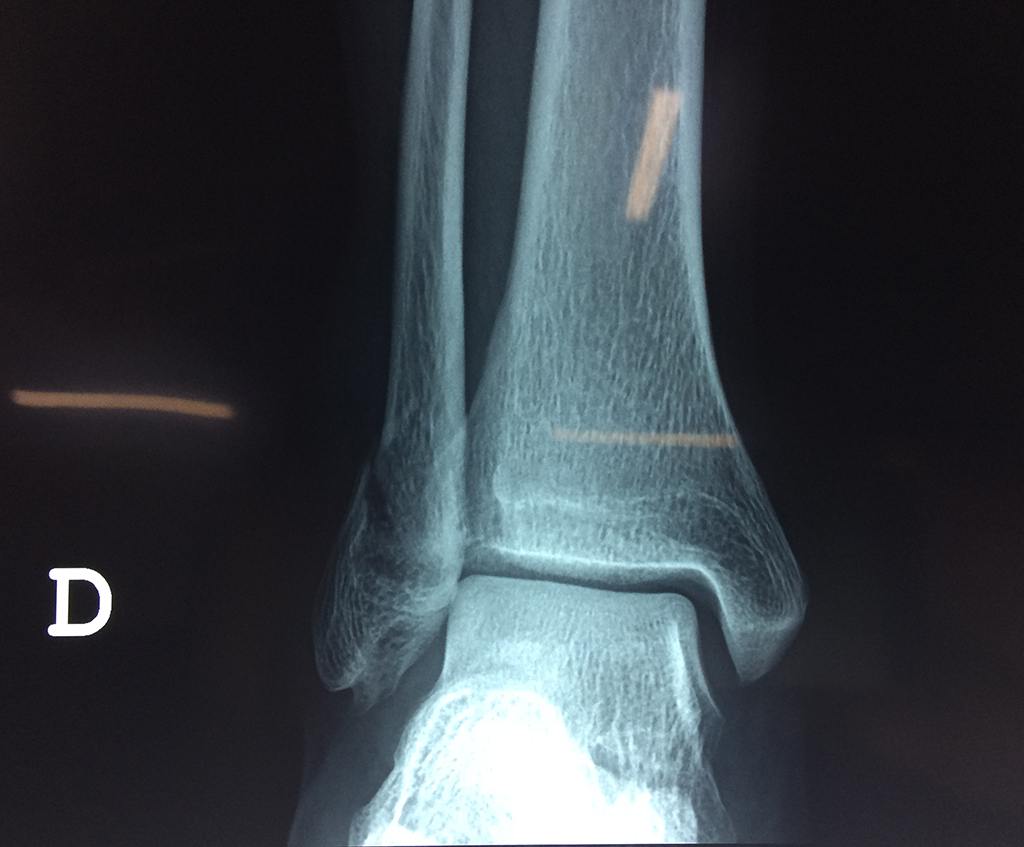

Una fractura de tobillo es la rotura de uno o más de los huesos del tobillo. Estas fracturas pueden ser:

Algunas fracturas de tobillo pueden requerir cirugía si:

- El médico cree que sus huesos probablemente no sanen apropiadamente sin cirugía.

- El médico considera que la cirugía puede permitirle una recuperación más rápida y confiable.